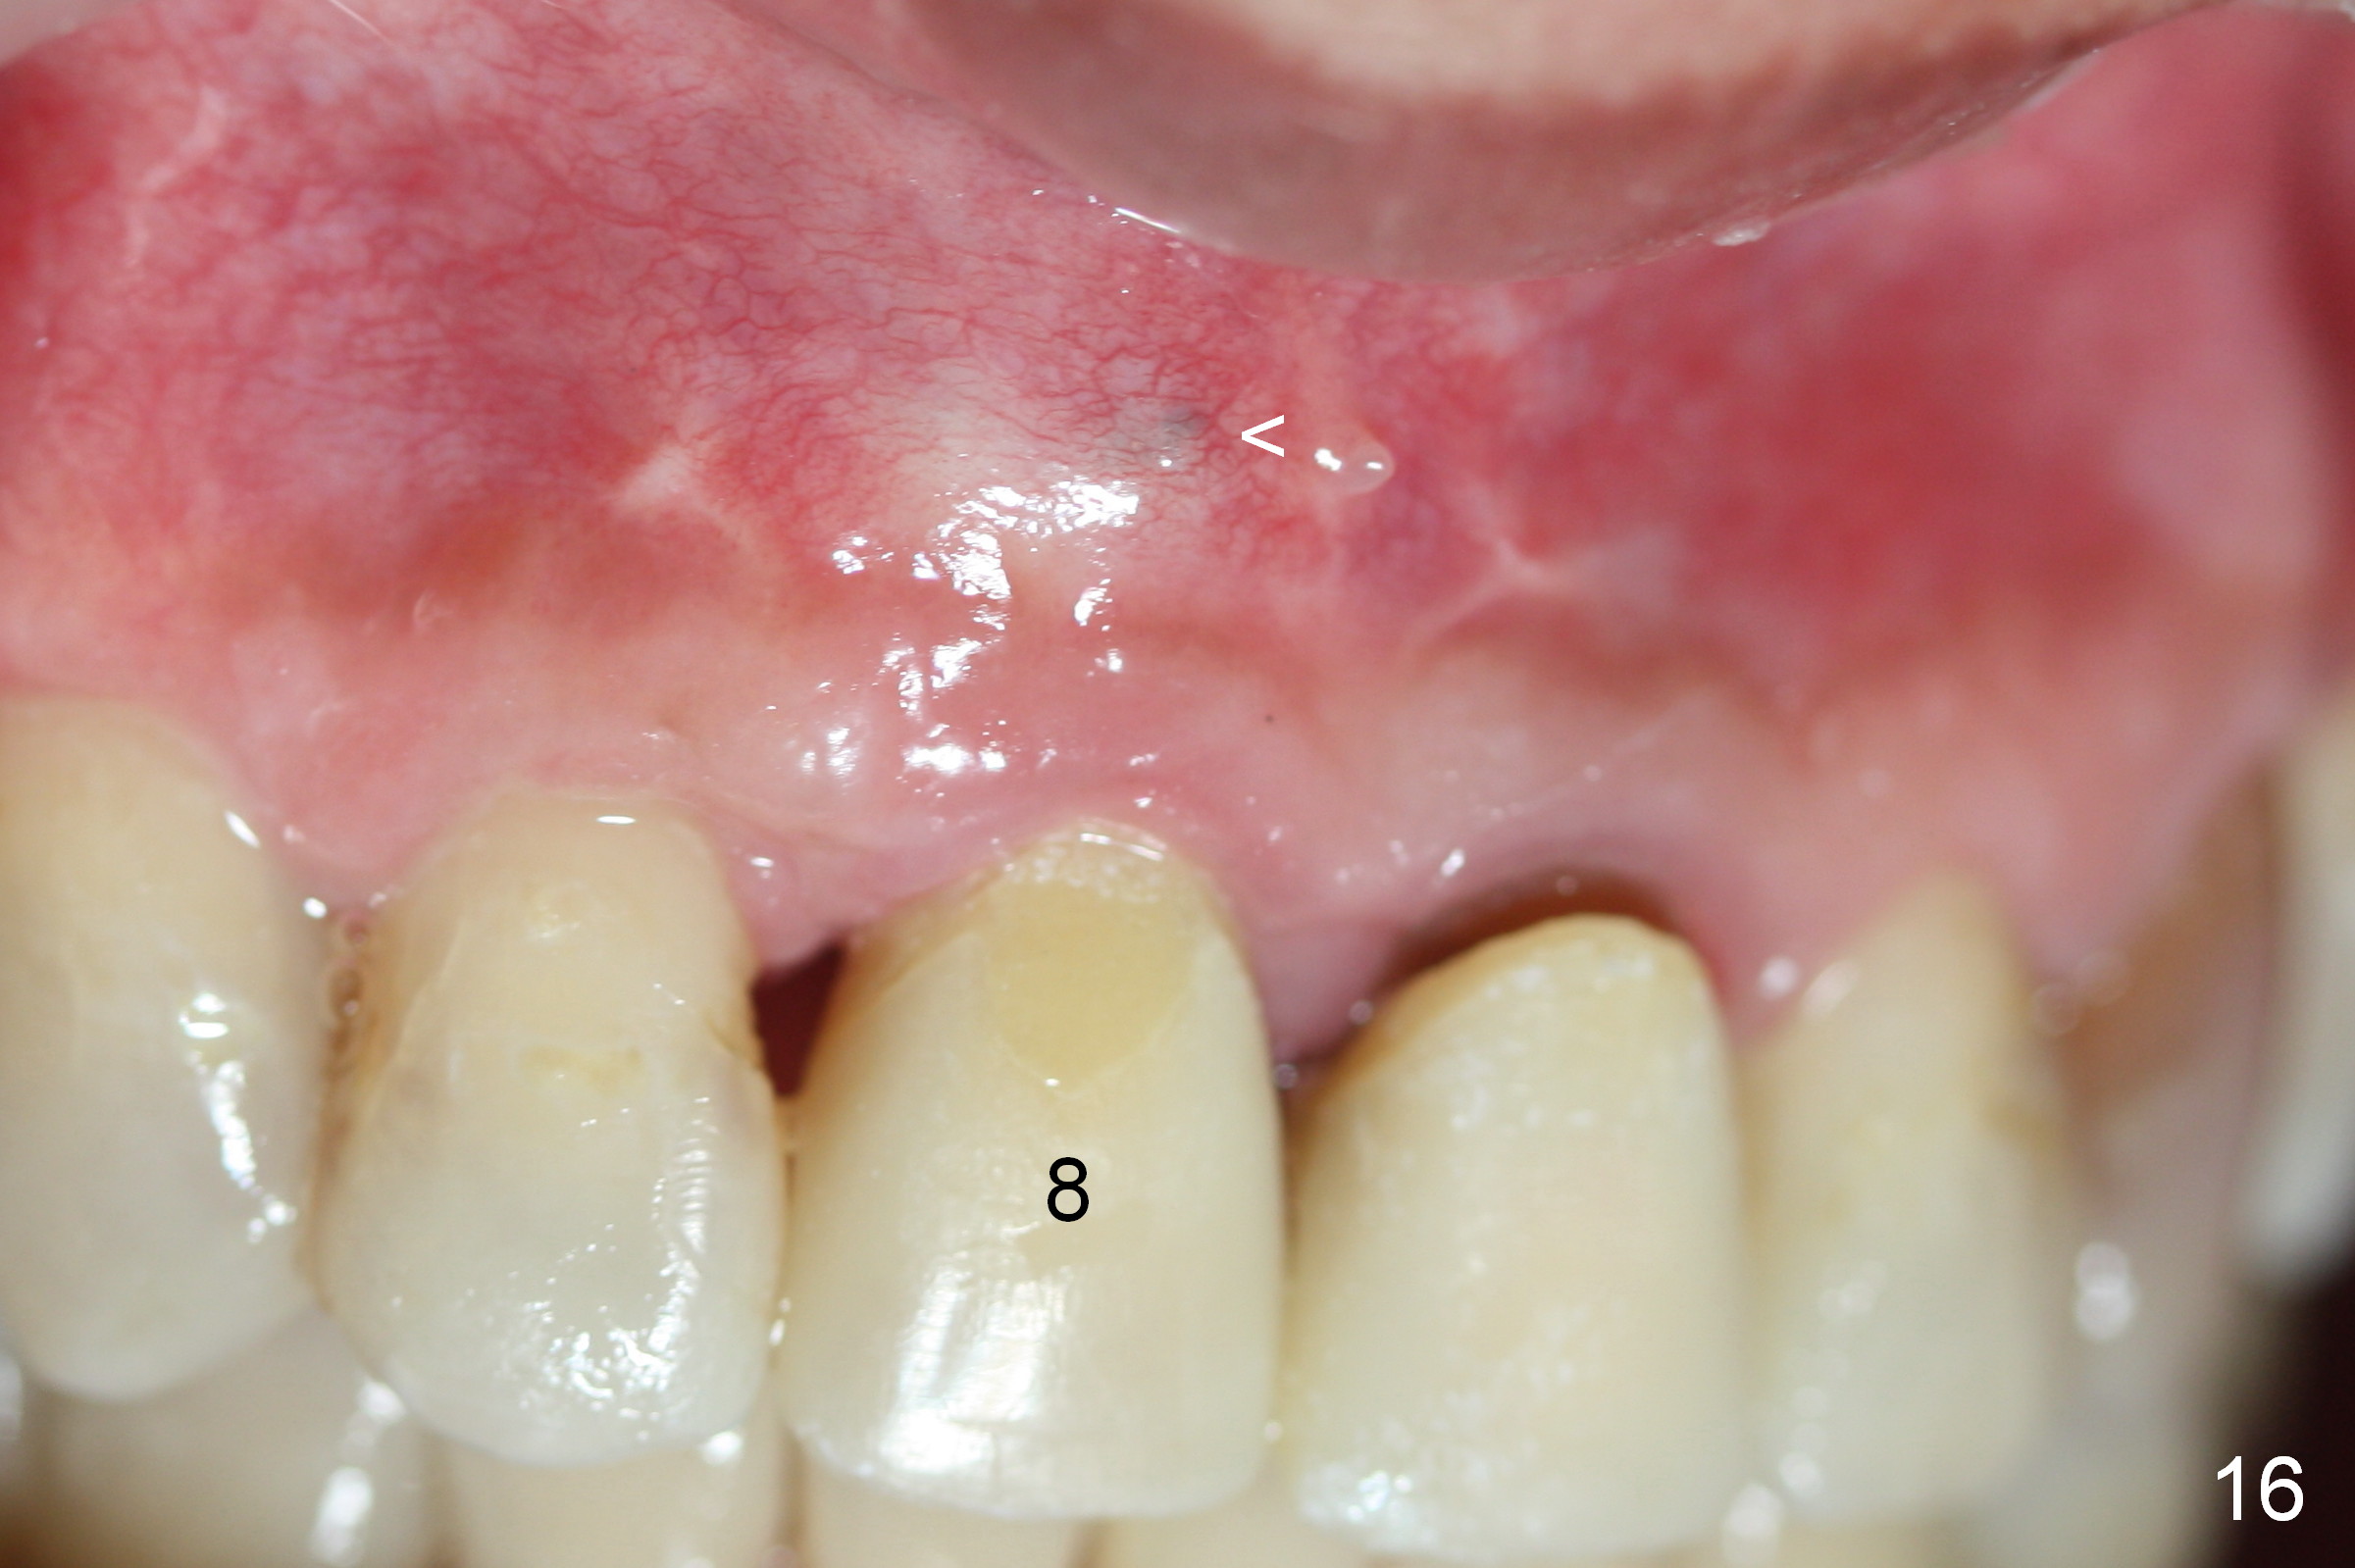

Nine months postop, the gingival margin is symmetrical over the provisional crowns at #8 and 9 (Fig.16).  There is no bulging or concavity associated with the implant at #8 (Fig.17).  Screw (Fig.16 <) removal is scheduled prior to final restoration.  The gingiva is healthy 1 year 7 months post cementation (Fig.18).